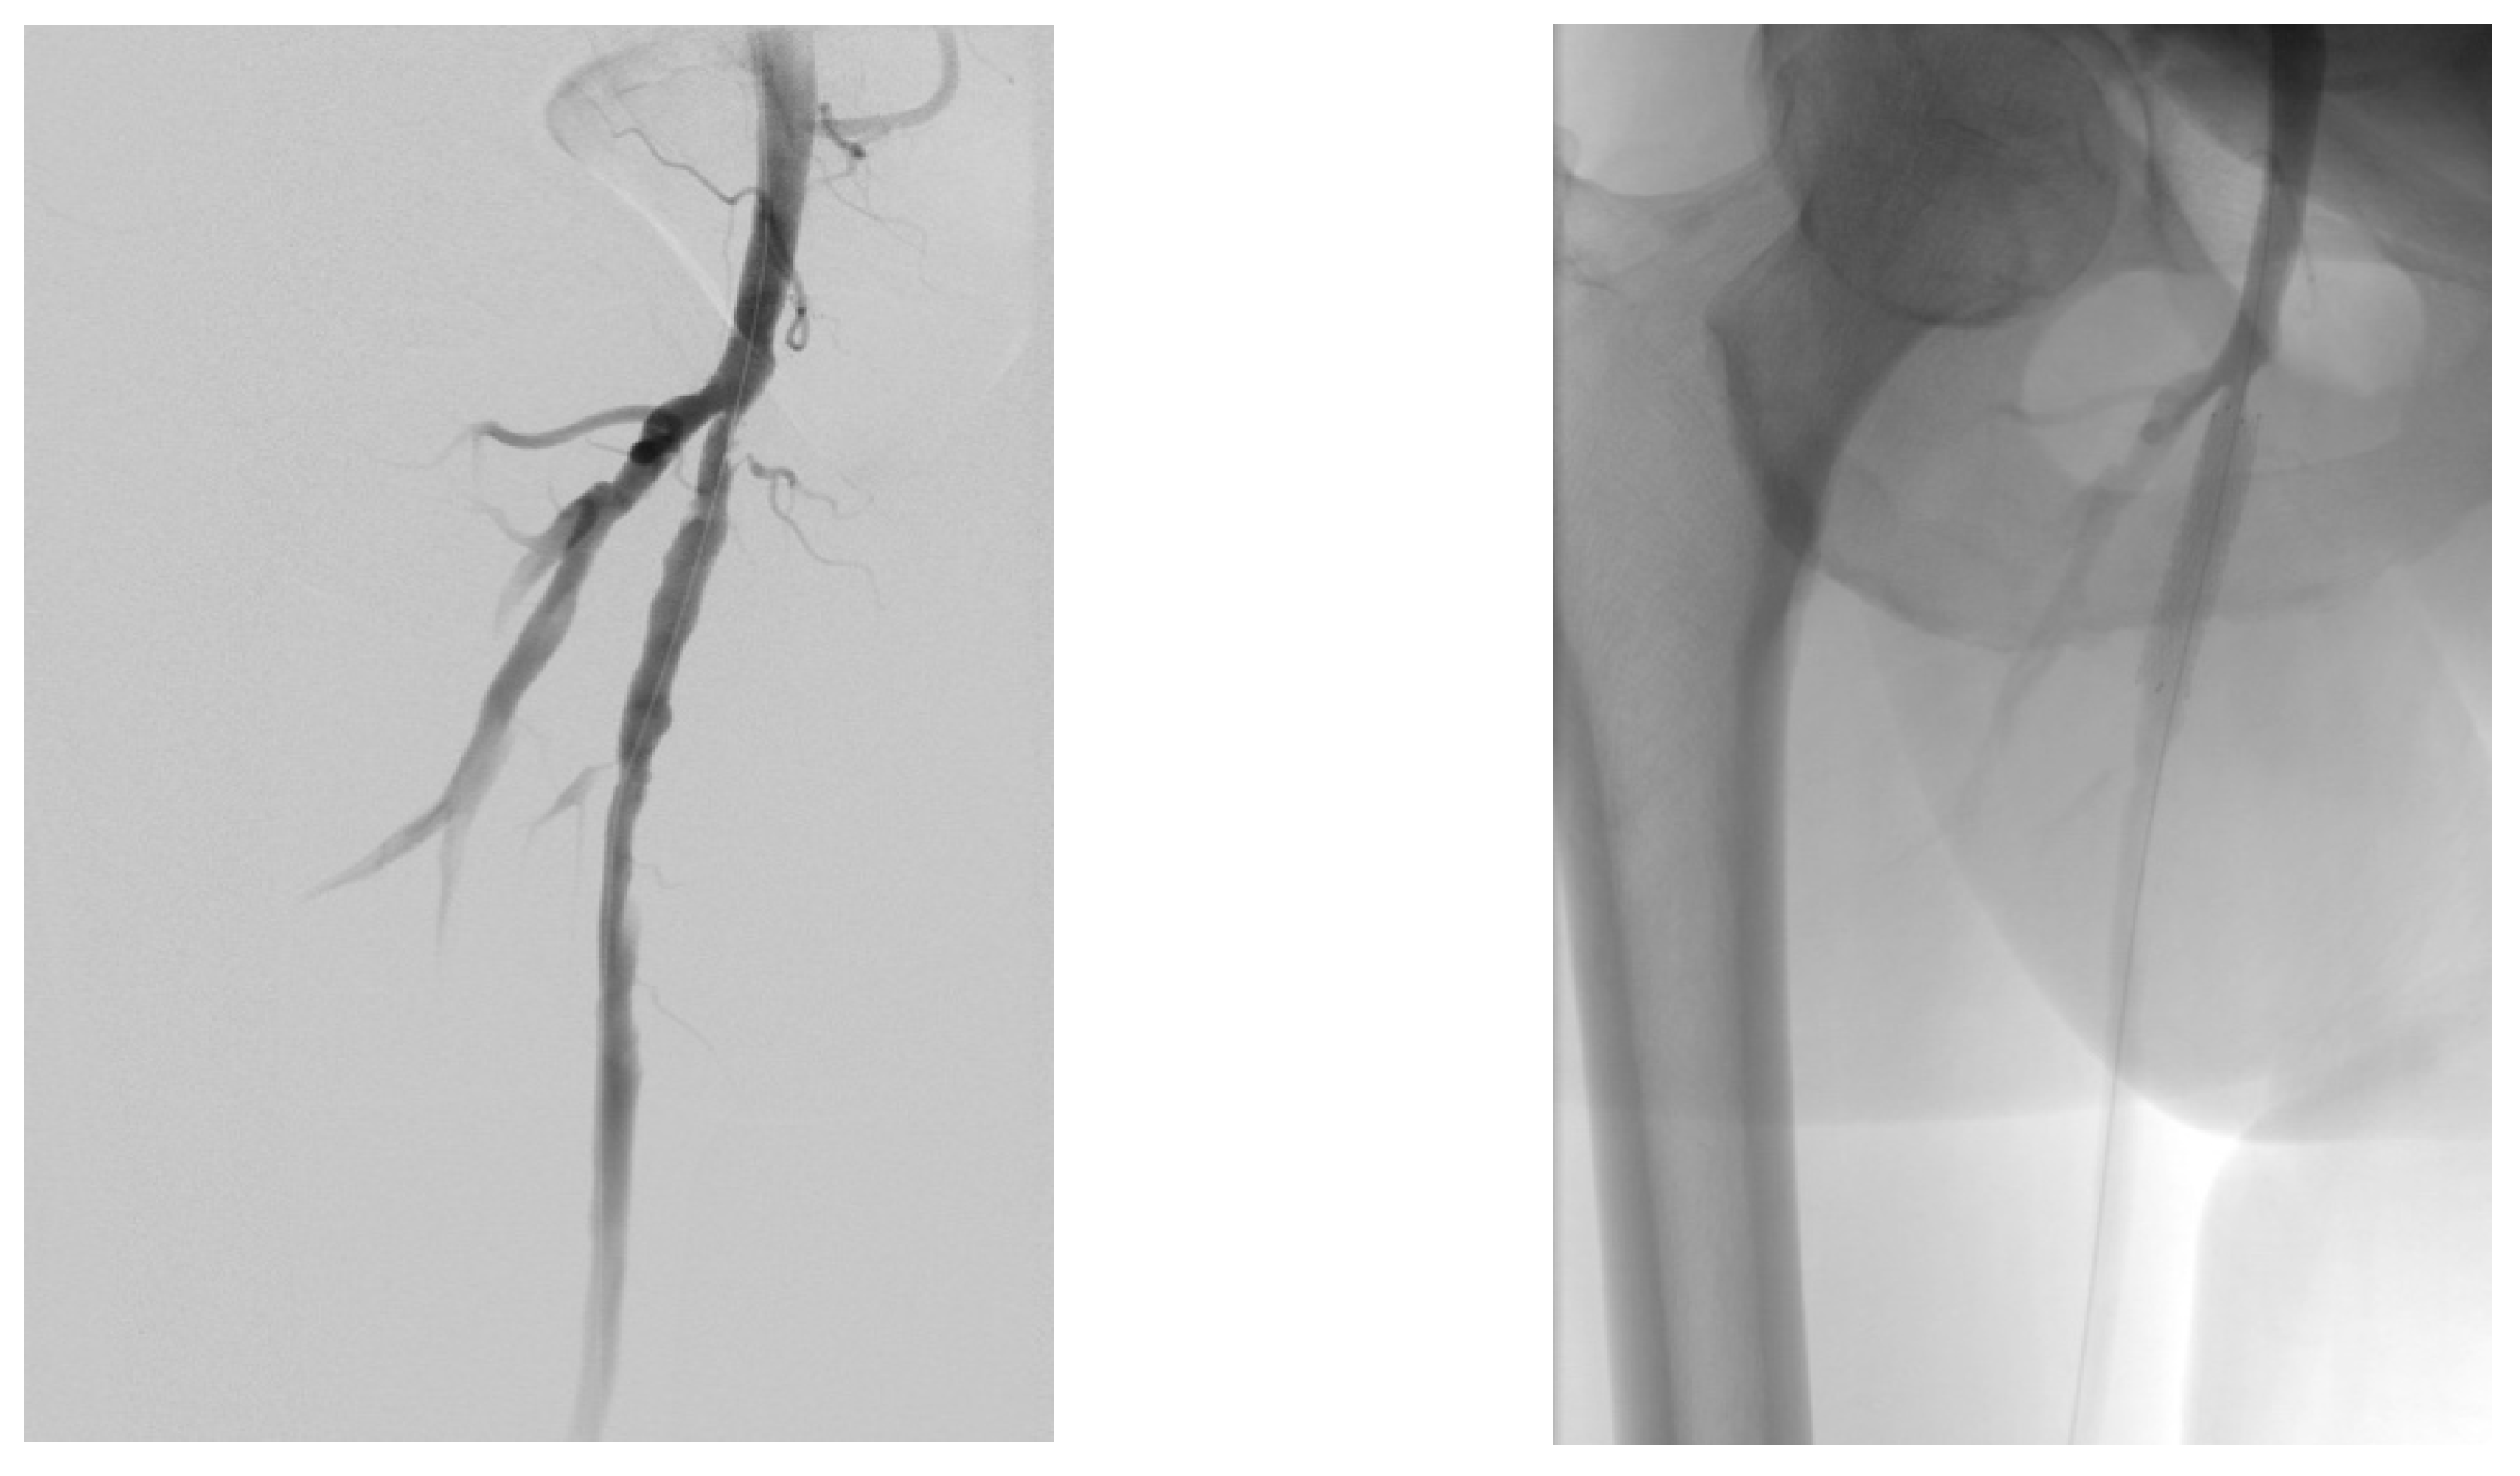

4.2. Case 2—Indirect Revascularization-Major Amputation